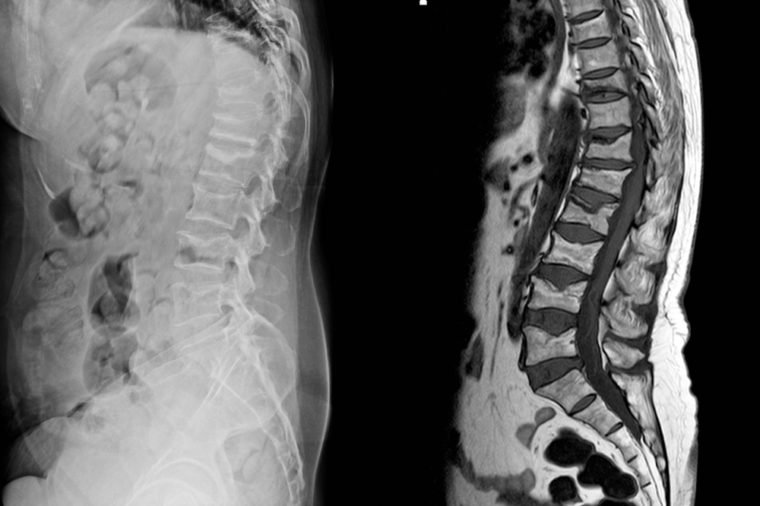

Nếu lưng bị tổn thương do tai nạn giao thông hoặc do va đập, bạn cần được kiểm tra y tế một cách toàn diện. Rất có thể bạn đã bị chấn thương cột sống hoặc một vấn đề nghiêm trọng nào đó. Chụp X-quang hoặc CT là những biện pháp kiểm tra giúp bác sĩ chẩn đoán chính xác tình trạng bạn đang gặp phải.